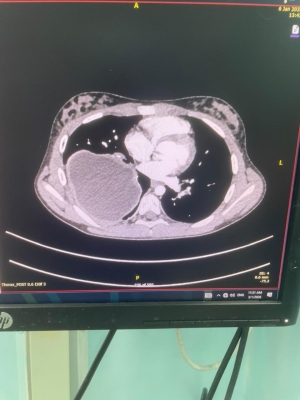

خبرني - أجرى فريق طبي متخصص من قسم جراحة الأطفال في مستشفى الملكة رانيا العبدالله للأطفال، برئاسة العقيد الطبيب وسيم المفلح، عمليتين جراحيتين لطفلتين كانتا تعانيان من وجود أكياس كلبيّة على الرئتين، بإستخدام المنظار الجراحي دون الحاجة إلى إجراء الجراحة التقليدية، من خلال ثقوب صغيرة في الصدر. وتُعد هذه العملية الأولى من نوعها على مستوى الخدمات الطبية الملكية.

وقال مستشار جراحة الأطفال العقيد الطبيب وسيم المفلح إن إستخدام المنظار الجراحي في مثل هذه الحالات لدى الأطفال يُعد تطوراً نوعياً ومميزاً على مستوى قسم جراحة الأطفال، لما يحققه من نتائج علاجية أفضل ويسهم في تقليل فترة الشفاء، والابتعاد عن الجراحة التقليدية وما قد يرافقها من مضاعفات، مشيراً إلى أن قسم جراحة الأطفال يسعى باستمرار إلى تطوير إستخدام تقنيات المنظار الجراحي في مختلف الحالات لمواكبة التطور الطبي في جراحة الأطفال والمسالك البولية للأطفال على مستوى المنطقة والعالم.